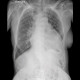

ALO Dokter, mari diskusi, apa saja hal yang dapat kita temui sebagai makna klinis pada fototoraks ini?